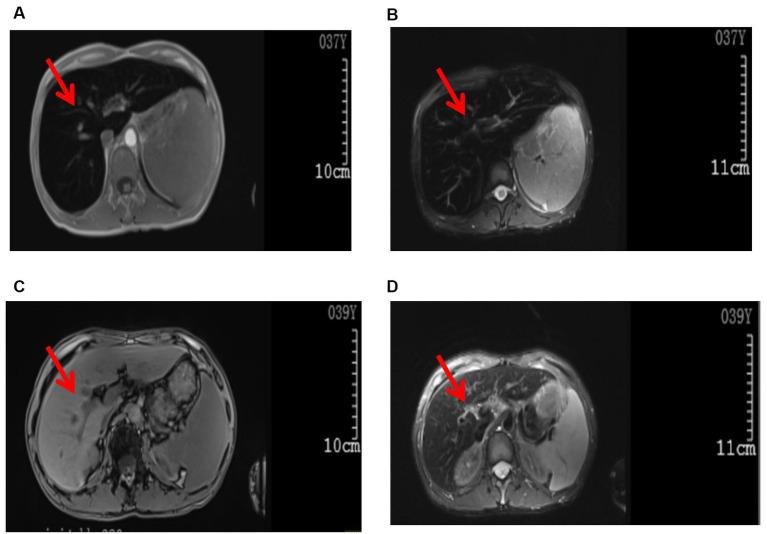

Case report: A rare case of hereditary hemochromatosis caused by a mutation in the HAMP gene in Fuyang, China.

Hemochromatosis, also known as siderosis, is a disease caused by excessive iron deposition in human organs and tissues, resulting from iron metabolism disorders. It is clinically characterized by skin pigmentation (bronze color), liver cirrhosis, diabetes, weakness, and fatigue. Additional symptoms may include arthritis, hypothyroidism, heart failure, and sexual hypofunction. Clinical manifestations can vary from person to person, with a few patients showing no clinical manifestations, which makes the diagnosis difficult for clinicians. In this case report, we described hereditary hemochromatosis related to a mutation in the HAMP gene in Fuyang City, China, as a reference for clinicians. Hereditary hemochromatosis is rarely reported in China. Clinicians in China have relatively insufficient knowledge of this disease, which leads to frequent misdiagnosis. In this case report, we describe hereditary hemochromatosis related to HAMP gene mutation in Fuyang City, China, for the clinician's reference.